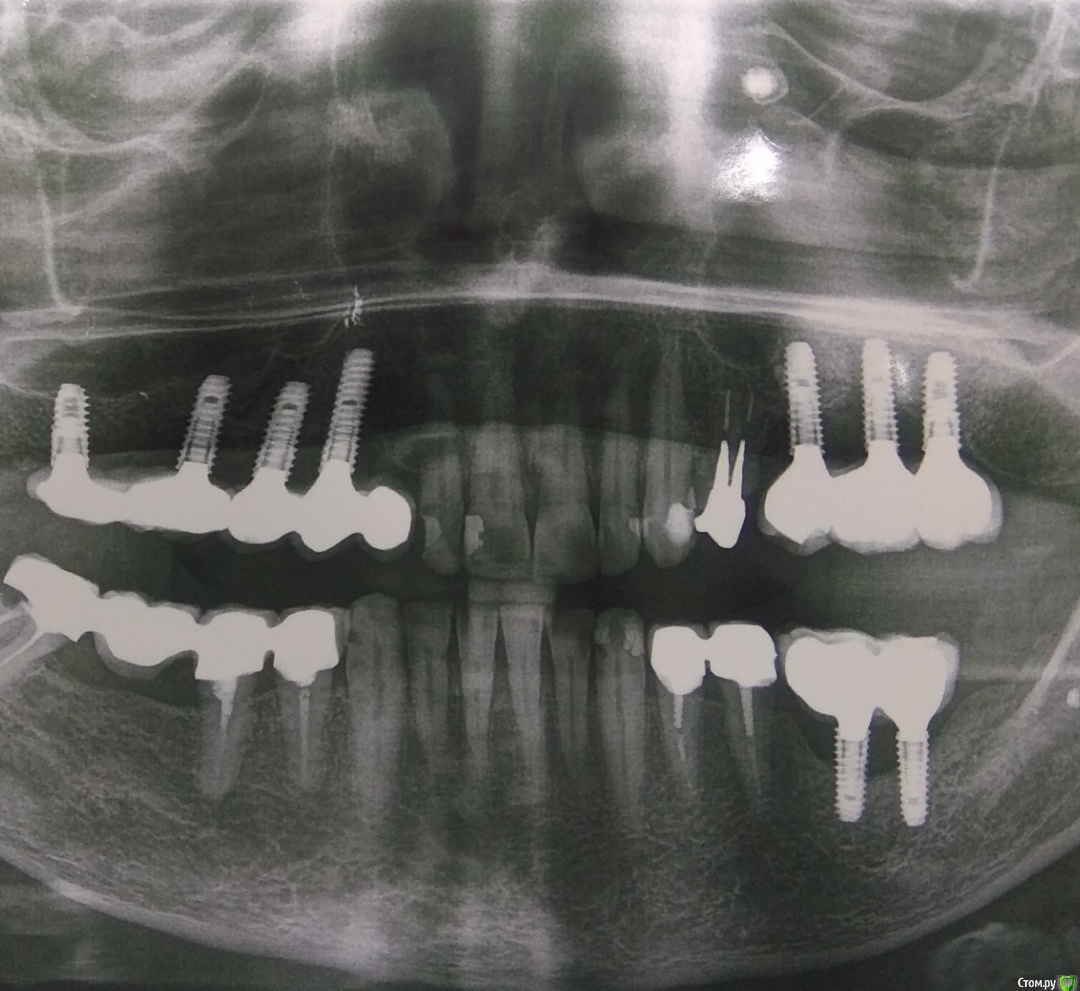

rimtar Опубликовано 16 ноября, 2020 Поделиться Опубликовано 16 ноября, 2020 года 4 , как сдали работу. синус/импланты мои. пациентка жаловалась, что не может жевать левой стороной, зубы не смыкаются. ортопед с техником что-то переделывали, но как оказалось без особого эффекта.недавно обратилась с жалобами на боли слева.орто:снял левую сторону, удалил подвижный 26 имплант.смутили очень короткие конусы, коронки держатся только на винтах:гигиена в порядке. есть проблемы с щитовидной, недавно тотальное удаление.буду благодарен, если укажете на причину , дабы вновь не повторить. Ссылка на комментарий

annda Опубликовано 16 ноября, 2020 Поделиться Опубликовано 16 ноября, 2020 (изменено) Что то мне кажется, что спиливали конусы для видимости пассивной посадки мостов. Оригинальная ли протетика, хотя тут уже это не имеет значения. Если только на винтах, то возможно и микроподвижность была с передачей напряжения на хрупкие шейки имплантатов, размер- то невелик. А оттуда и на кость, которая и ушла благополучно. Это если не видеть окклюзионных взаимоотношений антагонистов имплантат- имплантат , были ли смещающие контакты, ну и все такое. Справа тоже по ним звучит колокол.А что за система? Изменено 16 ноября, 2020 пользователем annda 2 Ссылка на комментарий

rimtar Опубликовано 16 ноября, 2020 Автор Поделиться Опубликовано 16 ноября, 2020 (изменено) про спиливание конусов ортопед сказал, но я не поверил, что такое практикуется. якобы проблемы с параллельностью так решаются.импланты осстем, остальное не оригинал, что именно- не знаю.и первый сегмент уходит, тоже понятно. Изменено 16 ноября, 2020 пользователем rimtar 1 Ссылка на комментарий

Дмитрий Л. Опубликовано 16 ноября, 2020 Поделиться Опубликовано 16 ноября, 2020 Шейки грязны,Сидит туго.Нет посадки, Сколы всюду.Неродные нам запчасти.Вот такое вот несчастье.Тихой ночью, как подруга,Ортопед сгубил хирурга. 13 Ссылка на комментарий

kramer Опубликовано 17 ноября, 2020 Поделиться Опубликовано 17 ноября, 2020 1. Выжигаемые абатменты -> негерметичное соединение-> периимпьантит2. Металлокерамика -> отсутствие эпителиального барьера Возможно есть проблемы с пассивностью посадки, хотя это само по себе не приводит к периимплантиту. В спиливании индексов также нет ничего страшного. Эти вещи могут привести к техническим осложнениям, а их не произошло. Мне кажется, основная проблема - негерметичное соединение В общем накосячил ортопед, но свалят на хирурга 1 Ссылка на комментарий

stommm Опубликовано 17 ноября, 2020 Поделиться Опубликовано 17 ноября, 2020 Имхо главная но не единственная причина. Нахрена глазурь под десной? Так или иначе будет карман. С мультиюнитами было бы намного безопаснее. Под десной должен быть титан или циркон. Но не керамика и кхс 2 Ссылка на комментарий